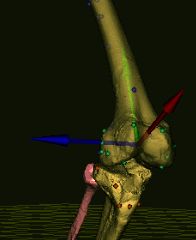

3D 골 모델에서 위치한 골격 랜드마크의 '''가상 촉진'''은 위 그림(오른쪽)과 같이 의료 영상에서 얻은 환자의 무릎 모델에서 확인할 수 있다. 뼈에 있는 색깔 구체는 촉진된 골격 랜드마크를 나타낸다. 이 방법은 정량화된 수동 촉진과 결합하여 특정 운동 작업(예: 걷기, 계단 오르기 등) 동안 관절 거동을 시각화할 수 있게 한다.

3D 골 모델에서 위치한 골격 랜드마크의 '''가상 촉진''' (오른쪽 이미지: 의료 영상에서 얻은 환자의 무릎 모델). 뼈에 있는 색깔 구체는 촉진된 골격 랜드마크를 나타낸다. 이 방법은 정량화된 수동 촉진과 결합하여 특정 운동 작업(예: 걷기, 계단 오르기 등) 동안 관절 거동의 피험자별 시각화를 가능하게 한다.[3]